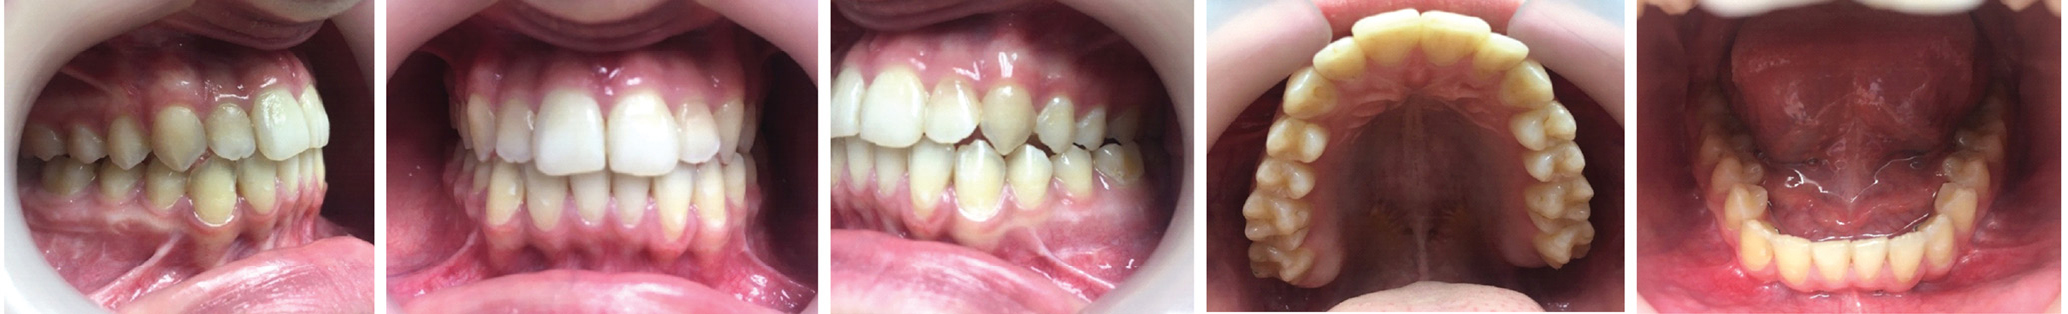

После проведения клинического обследования и антропометрии гипсовых моделей челюстей выявлено соотношение зубных рядов по III классу Энгля (мезиальная окклюзия) (рисунок 2), правильные форма и размеры зубных дуг верхней и нижней челюстей.

Рисунок 2. Смыкание зубных рядов (слева, спереди, справа), верхний и нижний зубные ряды пациентки Т., 18 лет, с мезиальной окклюзией гнатической формы до операции на нижней челюсти.

Через 6 месяцев после операции были сделаны повторные исследования (рисунки 6–9).

Рисунок 7. Смыкание зубных рядов (слева, спереди, справа), верхний и нижний зубные ряды пациентки Т., 18 лет, с мезиальной окклюзией гнатической формы после операции.